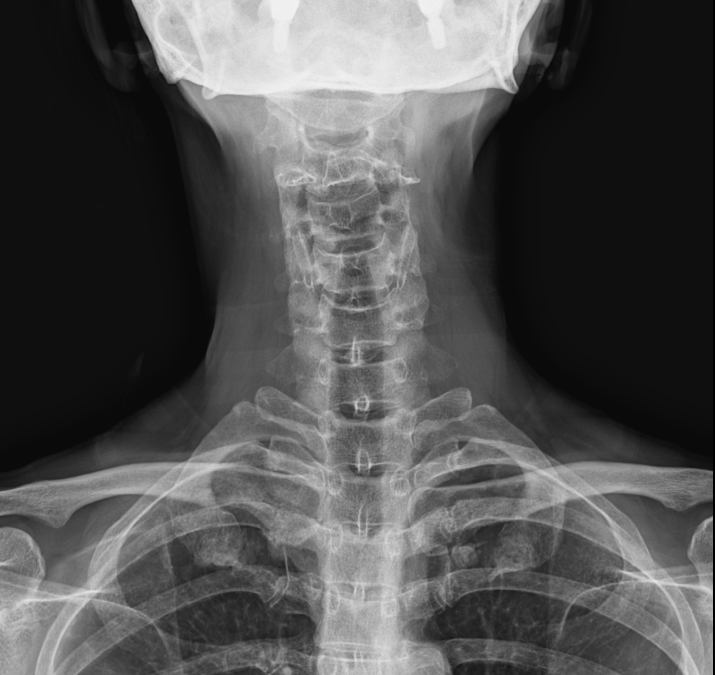

사경증도 경추가 휘어져서 생긴 후유증, 경추1,2번부터 교정을 해야한다. 그렇기 때문에 치아의 교합이 엉망이면 목이 틀어지게 되고 허리도 같이 틀어진다는 결론을 생각할 수 있습니다. 경추 1,2번은 항상 빠져있는데 그렇다면 경추와 요추가 항상 틀어지게 된다는 것을 또한 알 수 있습니다. X-ray, MRI 같은 2차원적인 검사 외에 척추와 골반의 특수 촬영을 한 영상을 보면 뇌척수액의 흐름에 따라 골반도 같이 움직이는 것을 볼 수 있었고 뇌척수액의 흐름이 원활하려면 척추가 바른 자세에 따라 뇌척수액이 잘 흐른다는 것도 확인되었습니다. 가부좌, 도인법과 같은 선법이나 양생법도 결국에는 척추를 바르게 해 주고 뇌척수액의 흐름이 좋게 열어주는 재활치료라고 할 수 있습니다.https://naver.me/FgiE6Sux

사경증이나 목디스크, 허리디스크 환자들을 그 아픈 부위만 물리치료와 시술, 도수치료를 하지만 허리 환자들이 40년, 50년을 허리치료를 받는 것으로 미루어 본다면 좁아진 목, 허리디스크 간격은 그대로 있고 통증만 앉히는 치료를 맴돌고 있는 실정입니다. 좁아졌거나 휘어진 척추들이 원래의 바른 척추모양으로 돌아가면 디스크가 닳아 없어졌어도 좁아진 상태에서 약물치료만 받는 것보다는 훨씬 통증이 부드러운 근본 치료가 될 것이라고 생각됩니다. 24마디 척추뼈 중에 1 마디뼈가 빠져있으면 전체 척추뼈들은 왁구가 잘 맞지 않은 부속이 안 맞아서 버려진 장난감 같은 척추 상태라고 할 수 있습니다. 고통받으시는 환자분들께는 매우 죄송한 표현입니다만 경추 1,2번 뼈가 빠져있다는 것을 가장 이해하기 쉬운 설명일 것입니다. X-ray 1장 찍고 이상 없다고 하는 것보다는 해부학적인 설명이죠.. 턱관절은 우리 몸의 모든 관절을 통제하는 마스터 관절(Master joint)입니다. 목뼈가 빠져서 척추가 틀어지기 시작해서 목뼈를 일자로 변형을 시키고 허리까지 변형을 주는데 요추 4,5번이 특히나 잘 좁아지는 부위인 것입니다. 흉추 15번 디스크는 제가 임상 20년 중에 아직은 못 봤습니다. S곡선이 있던 요추가 잘 튀어나가거나(전방전위증), 디스크가 좁아지고 붙어버리는 것이 오기가 쉬운 것입니다. 좁아진 요추를 벌리는 치료가 수술만 있는 것이 아닙니다. 경추 1,2번이 빠져있는지 확인을 하고 틀어져 있다면 경추 1,2번을 정렬(Alignment) 시켜주면 너무나 고맙게도 3번부터 24번까지 척추는 경추 1,2번과 인대, 근육을 따라서 차례차례 다시 줄을 서게 됩니다. 골반교정을 하고 Drop을 치고 근육을 풀고 할 일이 아니라 척추뼈를 움직이는 치료를 받아야 합니다. 그런데 이 경추 1,2번을 가장 많이 비틀고 누르는 것은 부정교합, 턱관절이라는 것이 중요합니다.